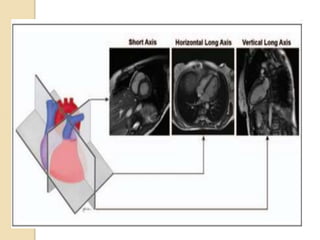

Cardiac planes  Thestandard cardiac planes are established using the scout images and include short axis view horizontal long axis (four-chamber view) vertical long axis (two-chamber view)

 These planesare prescribed along a line extending from the cardiac apex to the center of the mitral valve (long axis of the heart) using the axial body plane images.  The short-axis plane extends perpendicular to this true long axis of the heart at the level of the mid left ventricle.  The horizontal long(4 chamber) axis is generated by selecting the horizontal plane that is perpendicular to the short axis  The vertical long (2 chamber)axis is prescribed along a vertical plane orthogonal to the short-axis plane

Short axis view The short-axis plane extends perpendicular to this true long axis of the heart at the level of the mid left ventricle

4 chamber view The horizontal long axis(4 chamber view) is generated by selecting the horizontal plane that is perpendicular to the short axis